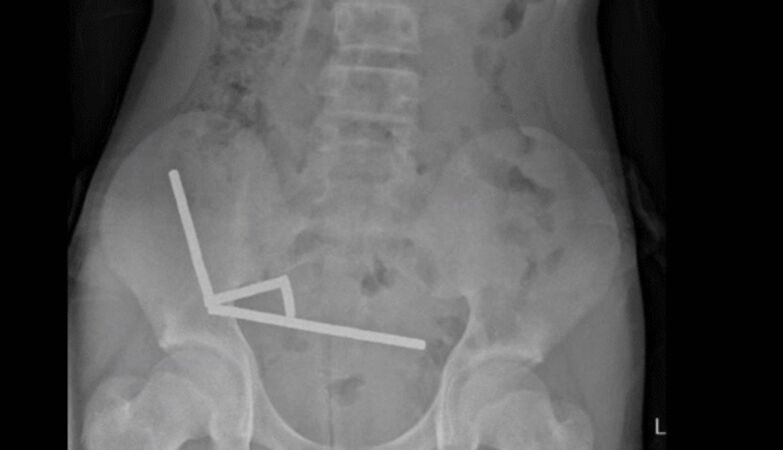

X-ray showing magnetic currents in the New Zealand teenager’s abdomen.

A 13-year-old boy in New Zealand had part of his intestine surgically removed after ingesting almost 200 high-powered magnets.

Once inside the abdomen, the small metallic objects came together, as the report describes, in a destructive way. By compressing, they were causing several areas of tissue to die due to lack of blood, in a phenomenon known as pressure necrosis.